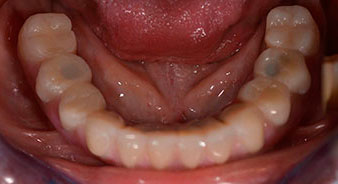

Following the time required for the osseointegration, the final impression of the implants could be performed and the final denture produced accordingly (Fig. 19 and 20). At this point, the dentist and patient were able to decide together whether to use a ceramic or acrylic veneer and a zirconium or metal framework. In this case, Dr. Pascu’s team decided on an acrylic veneer based on the unclear prognosis for the maxillary dentition and the fact that tooth 24 is elongated. This type of veneer is generally considerably easier to adapt and can thus be subsequently altered to reflect the new situation in the maxilla.